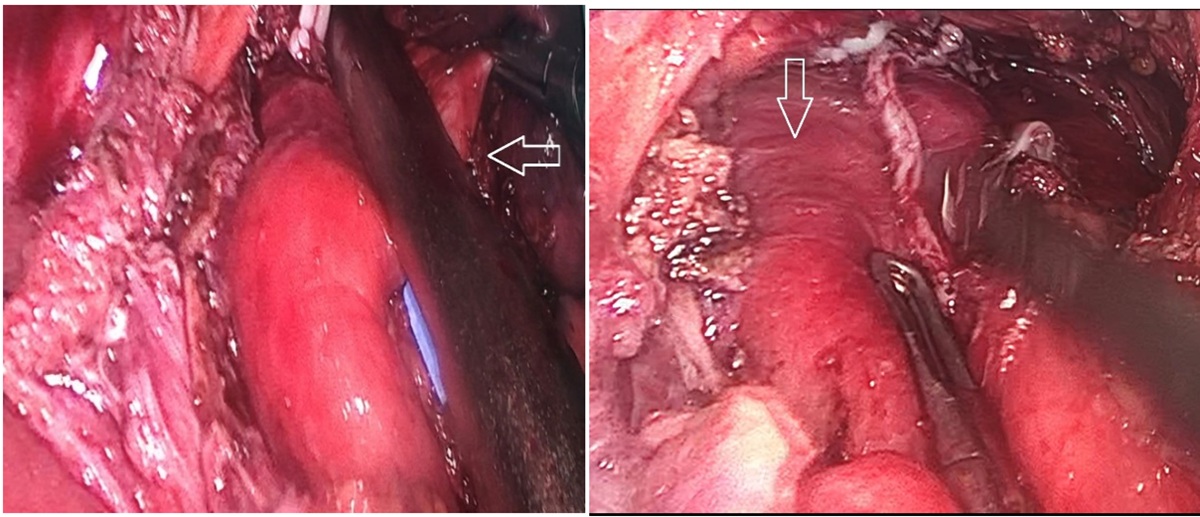

Bệnh nhân được chỉ định phẫu thuật nội soi cắt túi thừa thực quản kèm điều trị trào ngược dạ dày thực quản. Phương pháp vô cảm: Mê nội khí quản. Tiến hành cắt túi thừa, chống trào ngược bằng phương pháp Dor. Phẫu tích cắt dọc tới cổ túi chỗ nối thực quản dạ dày có động mạch đường kính khoảng 3mm chạy ngang đè vào ống niêm mạc ngang vùng cổ túi thừa, xử trí cắt động mạch. Thời gian cuộc mổ khoảng 4 giờ, lượng máu mất khoảng 20ml. Không ghi nhận tai biến trong lúc mổ.

Hình 2: Túi thừa thực quản được cắt bằng Echelon 60 ngang cổ túi